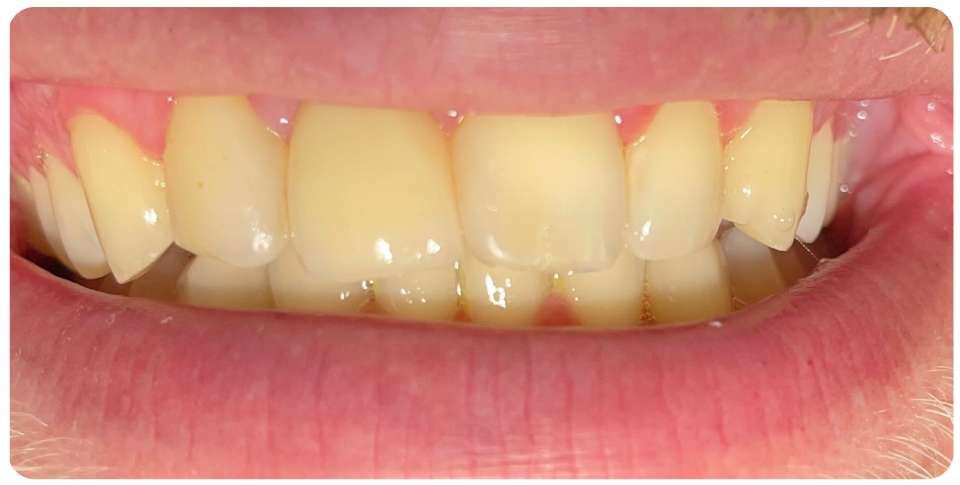

Complex Implant Rehabilitation

Complex dental implant rehabilitation is a highly effective solution for patients with extensive dental issues.

Such as severe bone loss, multiple missing teeth, cases involving tumor resection and reconstruction with vasculised bone grafts, gun shot injuries, with cleft lip and palate, jaw necrosis, post cancer oral rehabilitation.

- Improved Aesthetics

- Bring back lost confidence